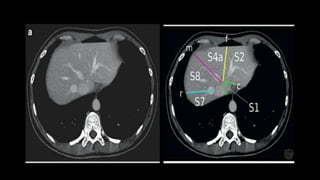

SEGMENTAL ANATOMY OF LIVER

• The French surgeon and anatomist Claude Couinaud divided the liver

into eight functionally independent segments

• allows resection of segments without damaging other segments.

• Each segment has its own vascular inflow, outflow and biliary

drainage.

• In the centre of each segment there is a branch of the portal vein,

hepatic artery and bile duct.

• In the periphery of each segment there is vascular outflow through

the hepatic veins.

• There are eight liver segments.

• Segment IV is divided into segment IVa and IVb according to Bismuth.

• The numbering of the segments is in a clockwise manner.

• Segment I (the caudate lobe) is located posteriorly.

• It is not visible on a frontal view.